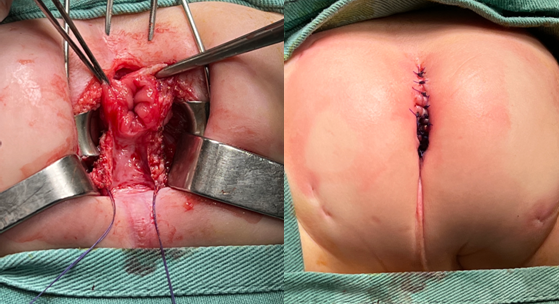

Se coordina biopsia rectal donde se evidencia imposibilidad de realizar tacto rectal con el paciente anestesiado, se coloca separador de LoneStar® donde se encuentra estenosis del canal anal. (Fig.2a)

De la técnica quirúrgica se coloca sonda vesical, posición en navaja. Se comprueba con estimulador la posición del ano en centro de complejo esfinteriano, se incide en forma sagital posterior desde punto donde se topografía punta de cóccix hasta margen posterior del ano. Se realiza abordaje por línea media hasta identificar fascia pre-sacra la cual se abre localizando el recto de características normales por debajo de ésta. Se libera recto por sus caras posterior y laterales, manteniendo cara anterior intacta, hasta lograr descenso sin tensión. (Fig.2b)

Se realiza una incisión a nivel de canal anal por su parte posterior sobre línea media, hasta llegar a recto sano, (Fig.3a) el cual formará la hemi-circunferencia posterior del ano. Se realiza plastia lateral con Polidioxanona 5,0 surget. (Fig.3b)

La anoplastia se realiza con puntos separados de Polidioxanona 5.0. (Fig.3b)

Se cierra incisión posterior sin dejar espacios residuales. Se pasa bujía 10 de Hegar sin dificultad.